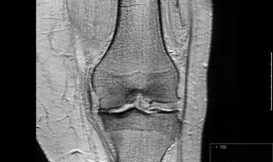

退化性關節炎長久以來都被視為是一項由老化帶來的致命傷,對症治療方式僅有紓解疼痛而已。事實上,這是一種完整獨立的關節疾病,多種可能導致軟骨損壞的危險因子已獲確認。退化性關節炎的起因機制研究相當活絡,研究員應該可以在未來幾年內找到新的治療標靶,並研發出對抗退化性關節炎的專門藥物。